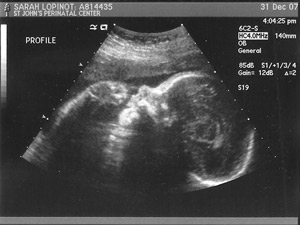

So on Monday, Sarah and I went in for another ultrasound. Can you believe that on tomorrow (Jan. 3) my wife will be 30 weeks pregnant? Only 10 or so weeks to go. Below is a great profile shot our ultrasound tech took of Chester Justin Jr. our unnamed son.

Though it’s obviously too early to tell anything for sure, it seems to me that he’s showing signs of my nose and Sarah’s chin. What do you think?